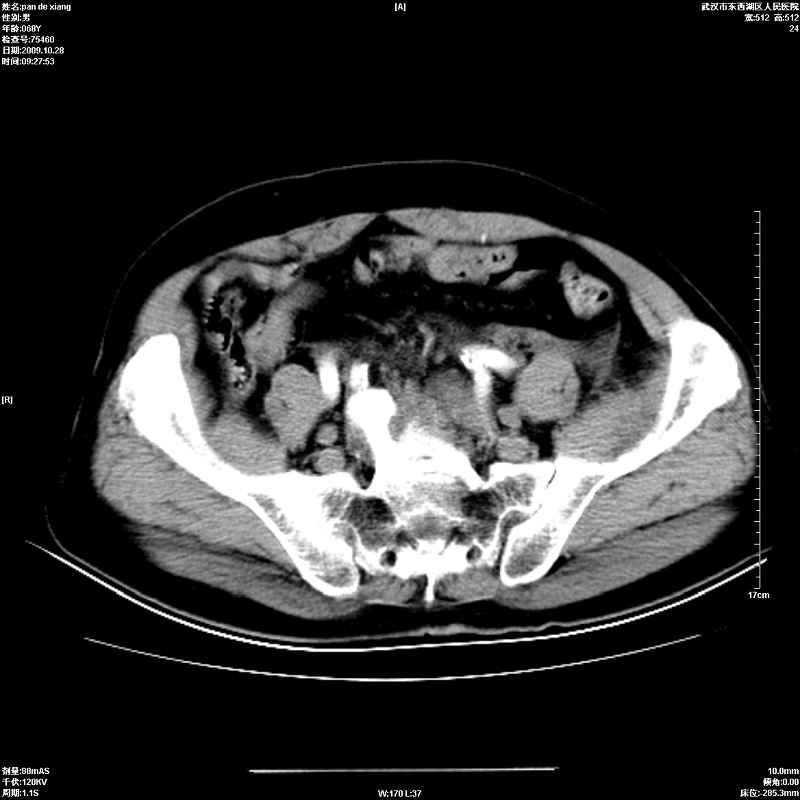

以下是引用杀毒软件在2009-10-28 20:41:00的发言:[br]结合临床考虑---白血病双肾改变或淋巴瘤。

以下是引用zxl51642在2009-10-29 9:59:00的发言:[br]结合临床“单克隆免疫球蛋白血症”,考虑双肾为继发损害并肾功能不全(尿中大量igg及少量iga、igm等大分子免疫球蛋白滤出所致继发损害),椎前软组织肿块为髓外造血。与浆细胞瘤有区别,平扫时有战友说的很清楚。